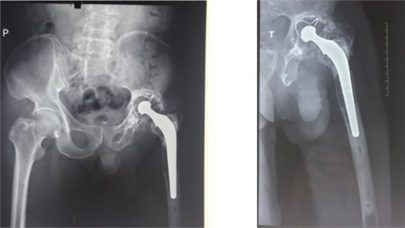

TS Nguyễn Quốc Dũng cho biết, trước đây với những BN này chắc chắn sẽ không thay lại được khớp, BN sẽ phải chịu tàn phế và đau đớn cả đời còn lại vì không có khớp chuôi dài phù hợp để làm chắc đoạn xương đã yếu.

Với loại khớp đặc biệt mới gồm 3 phần: Khớp háng thông thường + 1 phần chuôi 33cm đóng trong lòng ống tủy xuống đến hết ống tủy vít chốt giống như đinh nội tủy sử dụng trong gãy đoạn xương dài và đặc biệt có phần mấu chốt bên ngoài có thể chỉnh độ dài cho phù hợp với đoạn xương bị yếu. Loại khớp mới này sẽ là cứu cánh cho các BN bị thay lại khớp háng.